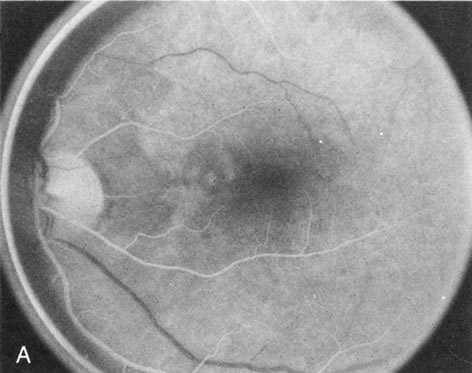

In the early stages of choroideremia, before choroidal atrophy is funduscopically obvious and when the picture resembles RP, FA indicates diffuse choroidal atrophy throughout the entire retina. Only the macular area remains preserved (Fig. 4A and B).

Fig. 4. Choroideremia and choroideremia carrier. A. The choroidal atrophy in this affected male is not apparent in the fundus. B. However, the angiogram shows diffuse atrophy of the choriocapillaris with persistent visualization of the larger choroidal vessels. C. This carrier female has peripapillary choroidal atrophy and diffuse pigment mottling. D. The patchy areas of focal choroidal atrophy that occasionally occurs in carriers is evident on angiography.